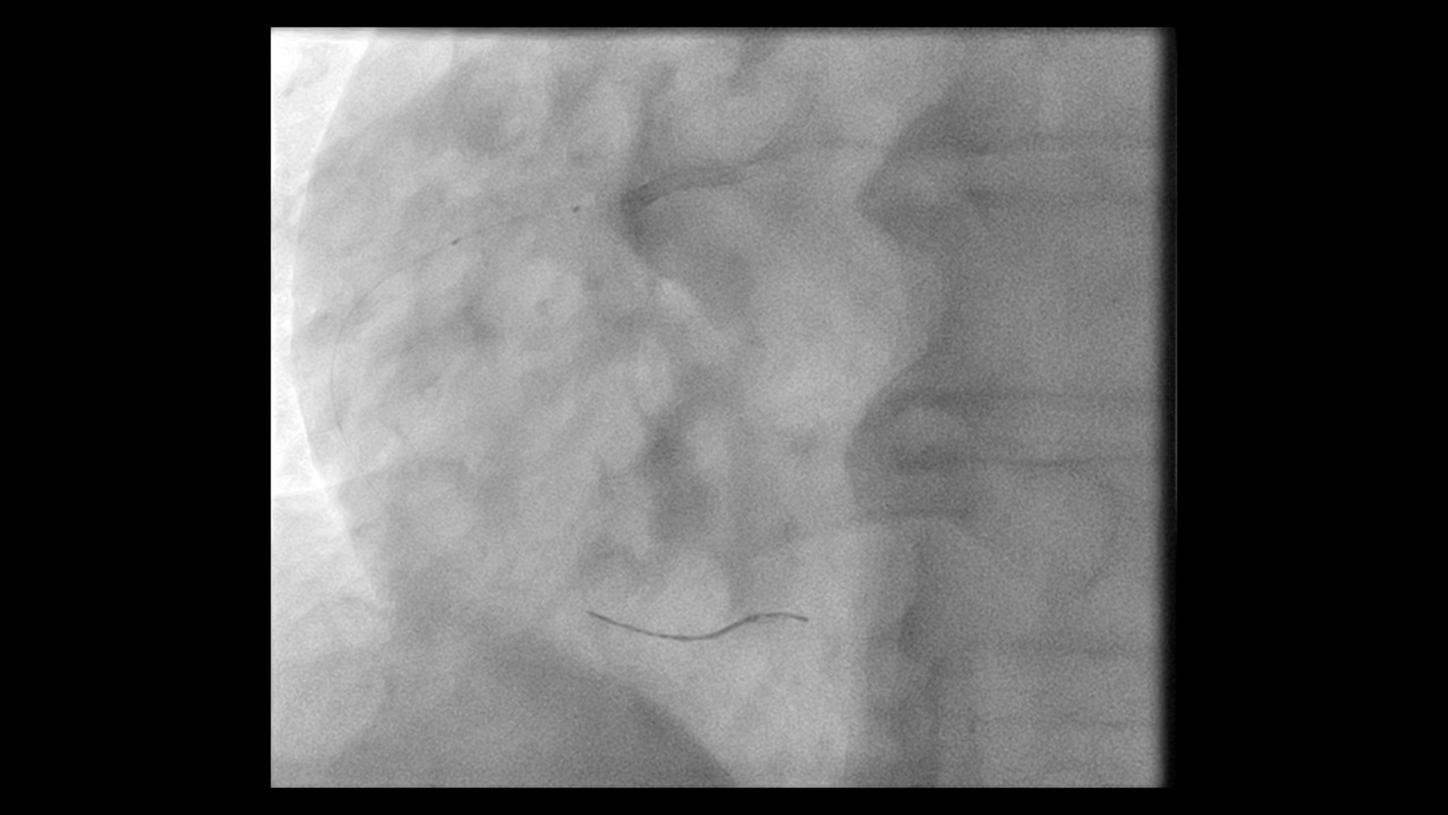

During minimally invasive procedures, it is critical to have a clear view of anatomies and devices. Yet complex imaging tasks or challenging patient conditions often impact image quality. OPTIQ AI delivers constant image quality1 defined by CNR in support of the ALARA principle, independent of patient or C-arm angulation. On top, an AI-powered algorithm reduces image noise in real time across different 2D imaging modes.

Make AI-powered imaging and clear insights your standard during interventions – with OPTIQ AI.